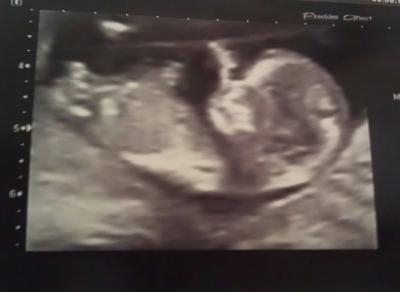

alles super. Alles gesund und putzmunter, hat am Daumen genukkelt. Sie hat erst vaginal geschallt und dann vom Bauch und da waren die Bilder noch toller. Oh man, ist das ein süsser Fratz. Und nun ist es endlich auch im Büro offiziell und ich darf nun endlich offiziell mich schwanger fühlen - was für ein Gefühl!! Ich bin so happy! Werde keine weiteren Untersuchungen machen lassen da meine Gyn meinte, es gebe kein gesünder aussehendes Embryo als meins ;-) Anbei noch ein Foto...

Bild zu wieder da und... - Forum für August - Mamis

Glückwunsch, das klingt traumhaft. Sicher ist es bissl gewagt von deiner Ärztin sowas zu sagen, andererseits ist sich glaube ich jede Schwangere darüber bewusst, dass immer ein Restrisiko besteht. Das Bild ist echt süß!!!! Alles Gute

Hallöchen, das hört sich doch Alles sehr gut an. Glückwünsch ! Das ist aber ein tolles US-Bildchen... dann freu Dich mal schön drüber und geniese den restlichen Tag ... LG Mone

Ein wunderschönes Foto. Super, dass alles in bester Ordnung ist!

4,6cm bei 11+3

Glückwunsch, Mega cooles Foto.

Das freut mich sehr für dich bzw. euch. Tolles Bildchen...echt süß.